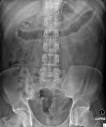

There is complete loss of haustral markings in the diseased section of colon, and the organ appears smooth-walled and cylindrical. The lead pipe appearance of colon is the classical barium enema finding in chronic ulcerative colitis. Learning Radiology - Ulcerative Colitis Ulcerative Colitis: Barium enema examination demonstrates loss of haustral folds in the entire descending colon with small ulcerations suggested. A middle-aged female with inflammatory bowel disease (IBD) (with mixed features of ulcerative colitis and Crohn s disease iron deficiency anaemia and recurrent Clostridium difficile colitis presented to the emergency department with complaints of abdominal pain, haematochezia and diarrhoea). One effect of lead pipe colon is that there is less surface area available to absorb water, which can lead to diarrhea and subsequently, dehydration.